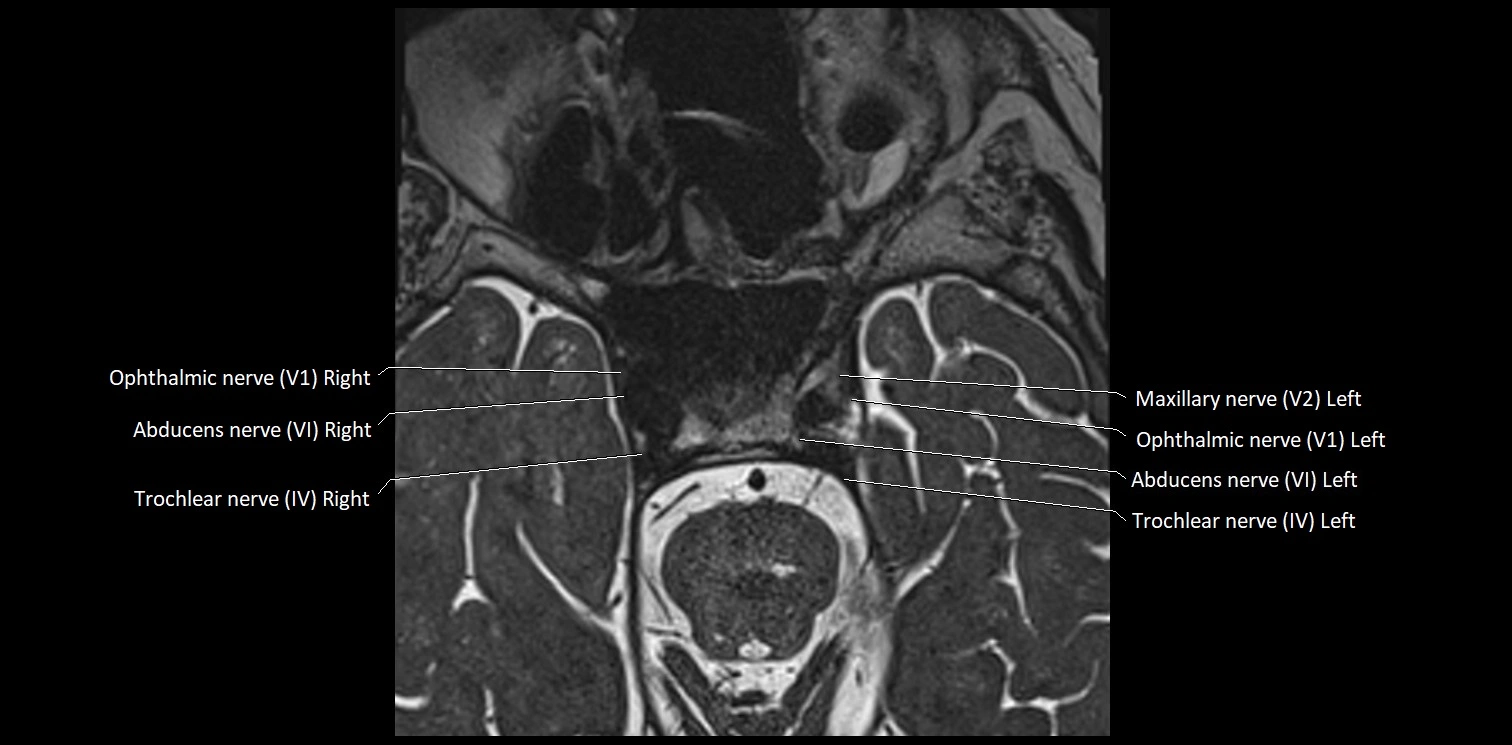

MRI Appearance

• The abducens nerve is a small, thin, linear structure

• Best visualized on high-resolution T2-weighted 3D MRI sequences (e.g., FIESTA or CISS)

• Seen as a hypointense (dark) line running from the brainstem at the pontomedullary junction, traversing the prepontine cistern, and entering Dorello’s canal under the petrosphenoidal ligament, then into the cavernous sinus, and finally the orbit

• May be challenging to visualize in standard MRI due to its small size

• Pathology may be inferred by absence, displacement, or enhancement of the nerve

MRI images

image